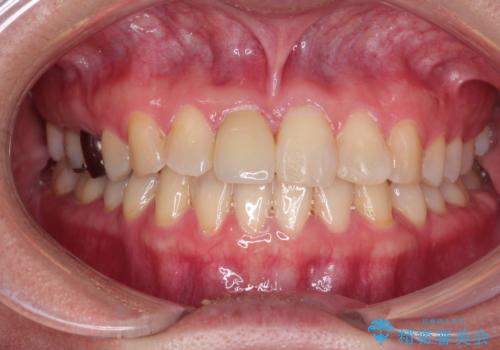

インビザラインにて矯正治療後の前歯のセラミッククラウン治療

- 前歯の歯並びが気になるとのことで来院されました。

右上の1番目の歯が内側に入り込んでしまっており、その歯がの先端がすり減ってしまっていました。

インビザラインによる矯正治療で前歯の歯並びを改善し、セラミッククラウン装着により歯の形態の回復をする計画としました。

矯正とセラミックを併用することで、より完成度の高い状態に仕上げることができました。